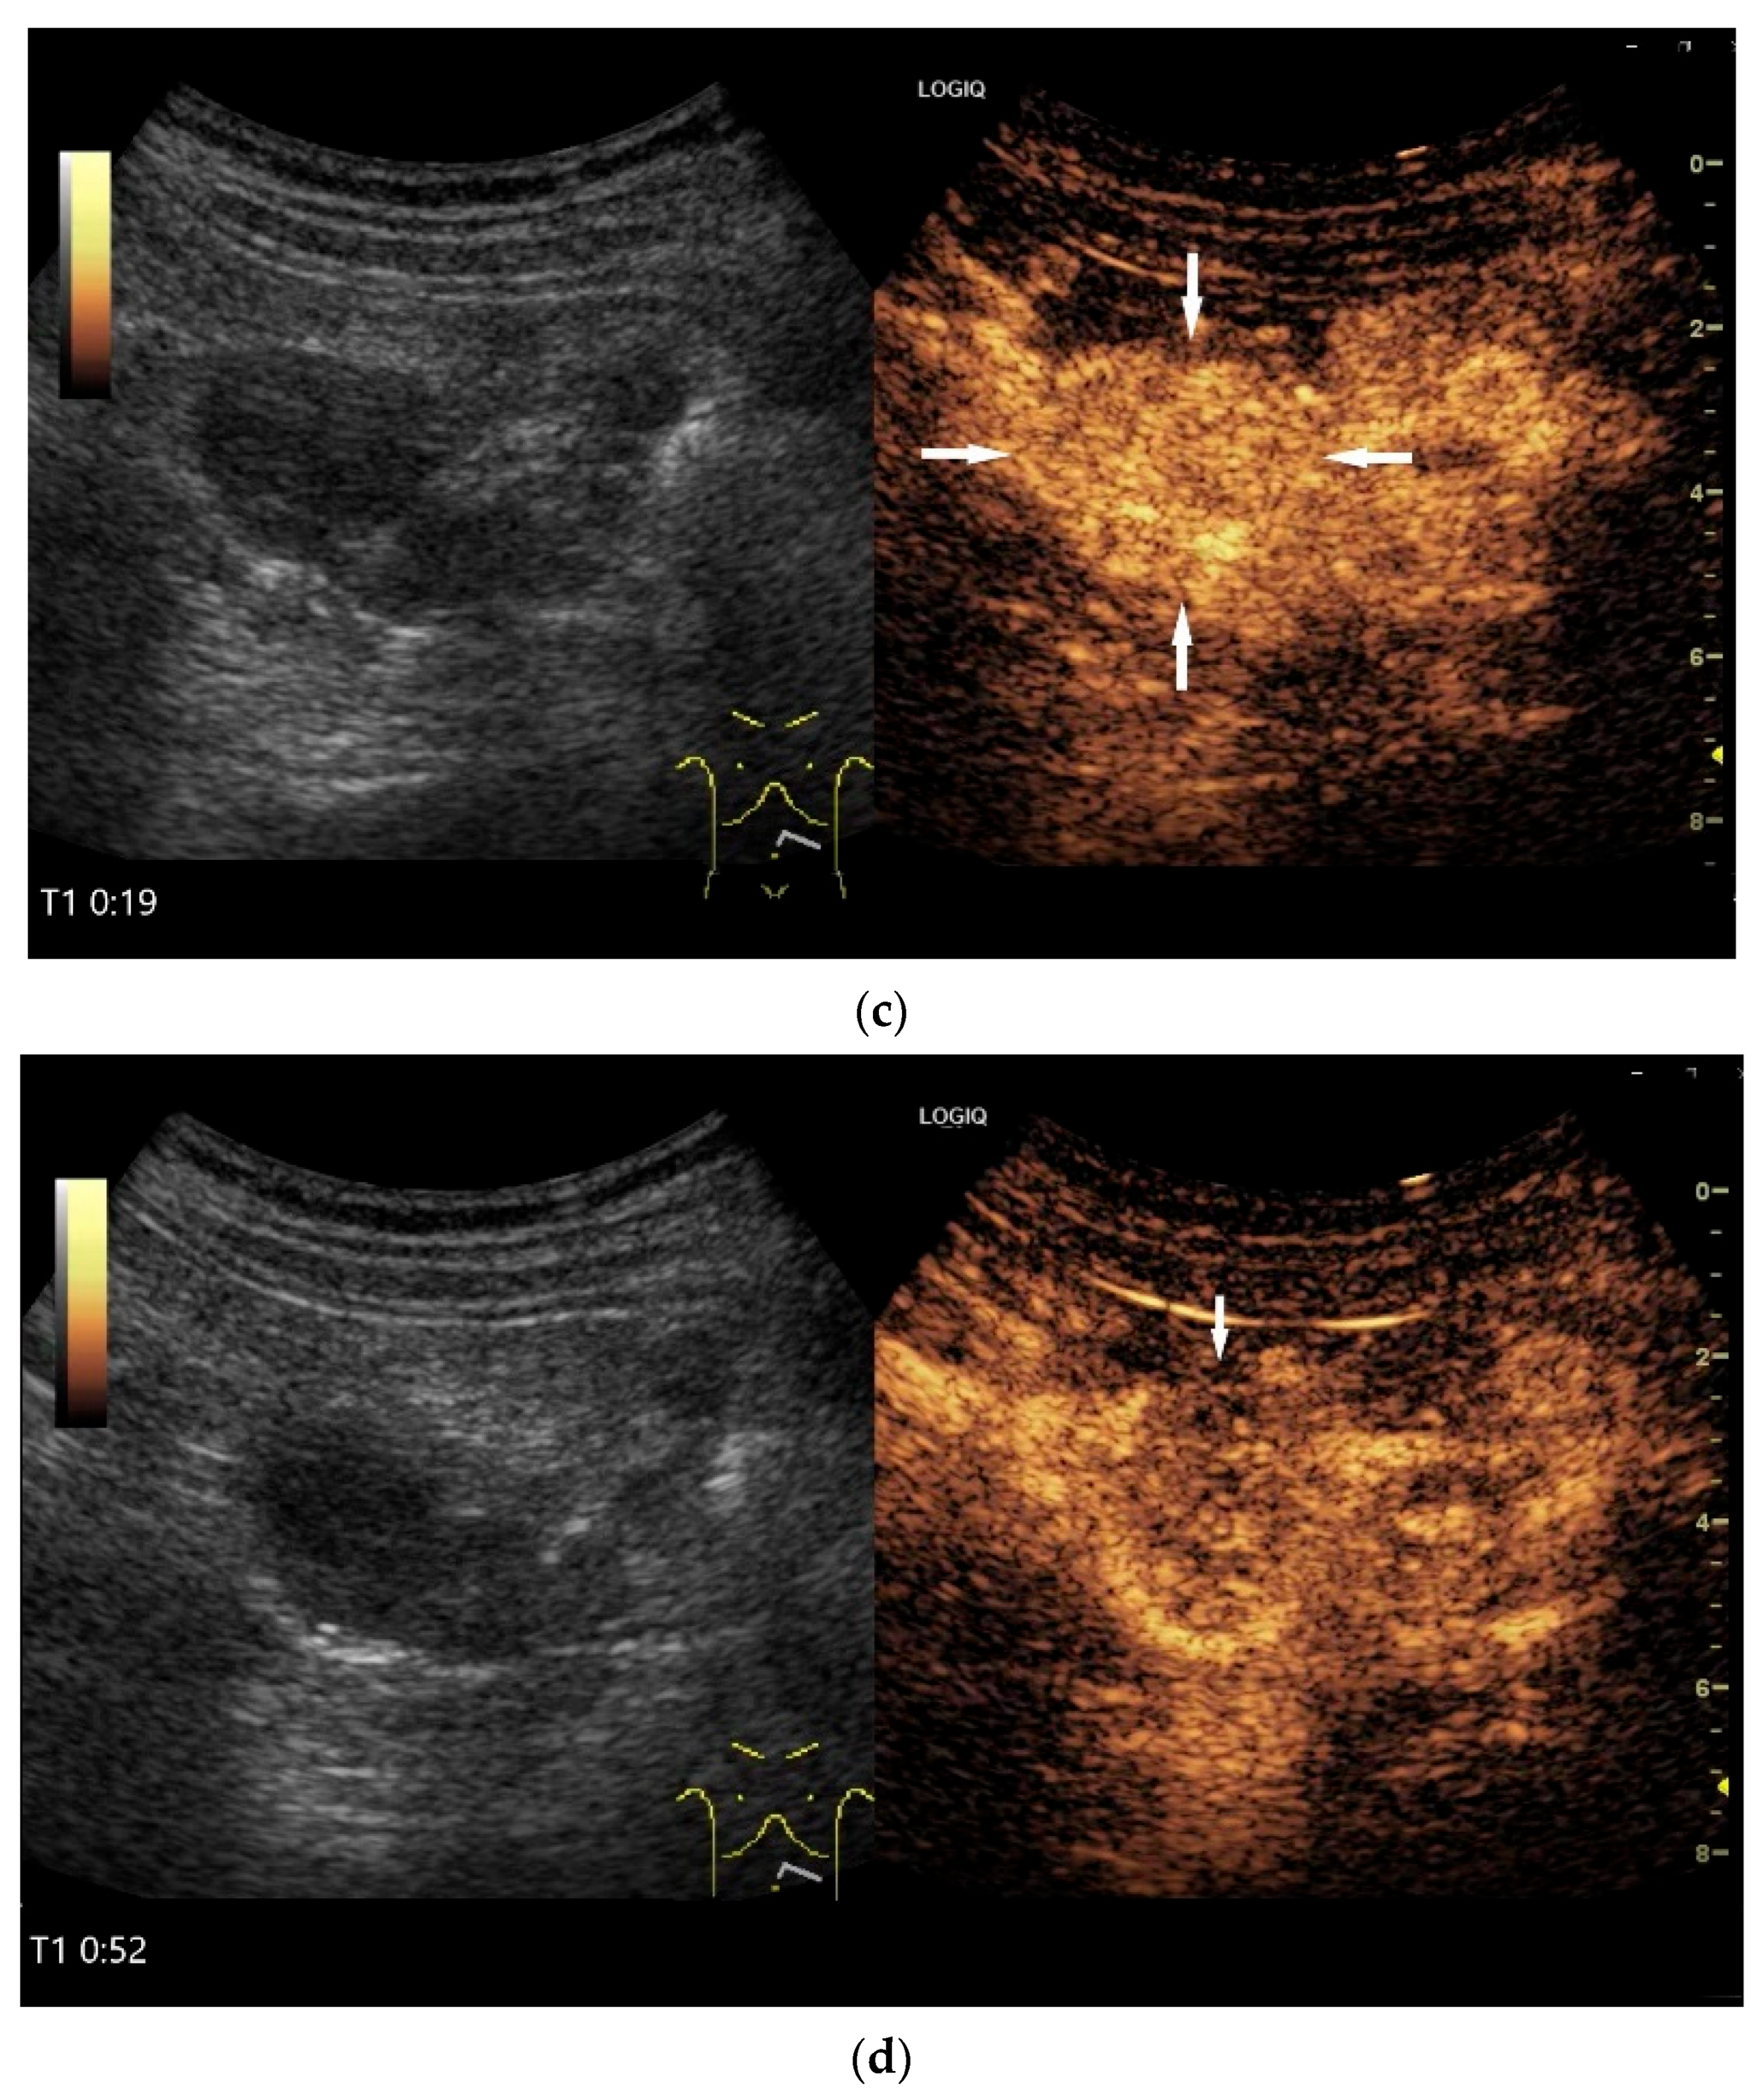

Figure 10.

Diffuse large B-cell lymphoma (DLBCL). In the right mid-lower abdomen, a large, smoothly circumscribed mass is present around the ileum (“pseudo kidney sign” (a)). Using a high-resolution linear transducer, the mass appears smoothly circumscribed and almost anechoic (b). The ileum runs centrally, and the echogenic wall is clearly defined (c). This wall does not merge into the mass. Since the mass is almost anechoic, it is also difficult in different transducer positions to distinguish whether it is a liquid lesion or a solid mass (b,c). CEUS with 2.4 mL SonoVue (9 MHz linear transducer) shows homogeneous arterial enhancement (d), but the intensity decreases with time in the venous phase (e). The ileal wall enhancement centrally within the mass is more intense than that of the tumor (d,e).